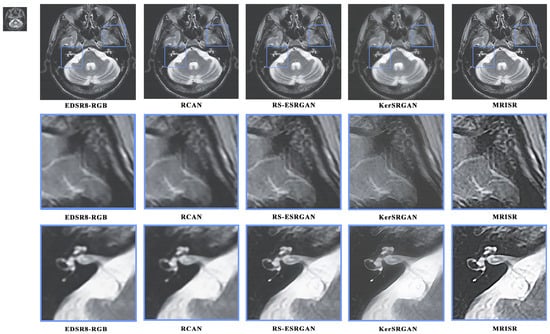

Figure 16 and Figure 17 present a visual comparison of images generated by different algorithms, with the objective of conducting a comprehensive analysis of the performance of various models in the task of image super-resolution reconstruction. Through a detailed examination of images featuring complex terrains, it is evident that, due to the inherent limitations of traditional interpolation algorithms, such as the bicubic method, the processed images exhibit a high degree of blurring and smoothing, ultimately resulting in a significant loss of detailed information. In contrast, while advanced deep learning models, like EDSR8-RGB, RCAN, and RS-ESRGAN, have demonstrated notable advancements in image super-resolution reconstruction, they still exhibit certain deficiencies in accurately distinguishing noise with sharp edges, leading to blurred outputs and unsatisfactory detail recovery. The proposed MRISR model in this paper, however, introduces innovative noise estimation and reconstruction strategies, resulting in generated images that exhibit clearer boundaries between objects and backgrounds, along with more accurate detail recovery. This indicates that our estimated noise distribution is closer to the real noise, thereby effectively enhancing the overall quality of image super-resolution reconstruction. When compared with models such as EDSR8-RGB, RCAN, and RS-ESRGAN, the results of the proposed MRISR model exhibit significantly improved visual clarity, richer details, and no blurring artifacts, fully demonstrating its superiority and effectiveness in the task of image super-resolution reconstruction.

Information 15 00655 g016

Figure 17. Visual comparison of the generated images.

Information 15 00655 g017